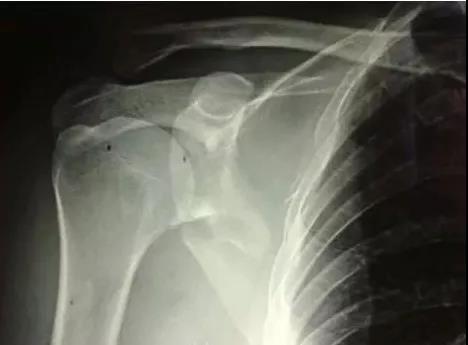

1)肱骨近端骨折

脱位伤及腋神经、血管等,或者由于肱二头肌长头腱卡压无法复位,立即手术。